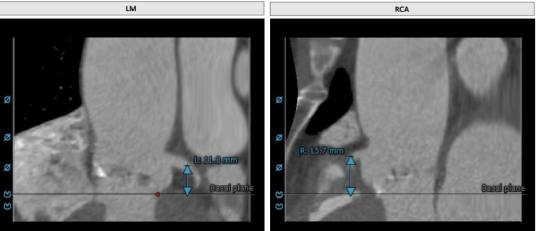

Annulus:25.8mm

LVOT:27.1mm

STJ 30.6mm

升主动脉:38.4mm

LM:10mm

RM:12.2mm

CT分析

以3个窦消失最低点确认的平面作为虚拟瓣环平面初步筛选瓣膜尺寸。自展瓣参考周长得出的Annulus直径,该病人为25.8,根据自膨胀瓣膜特点需要oversize,初步判断为29/32瓣膜。LVOT直径大于Annulus,短径24mm,足够限制瓣膜,提供锚定支撑力。STJ高度足够,可提供足够空间给原有瓣叶,过宽的STJ则无法提供释放中锚定支撑力。

窦部的空间与左右冠脉开口高度结合瓣叶形态,是否增厚可以初步判断瓣叶是否会在瓣膜植入后遮挡冠脉开口造成急性的冠脉堵塞。该病人左冠开口略低,且钙化集中在右冠和无冠窦,判断冠脉风险较高。需术中球扩判断是否进行冠脉保护。

升主动脉未见增宽,心脏角度合适极重度钙化,多集中在基底部位二叶瓣重度钙化THV需要downsize选择26/29瓣膜。